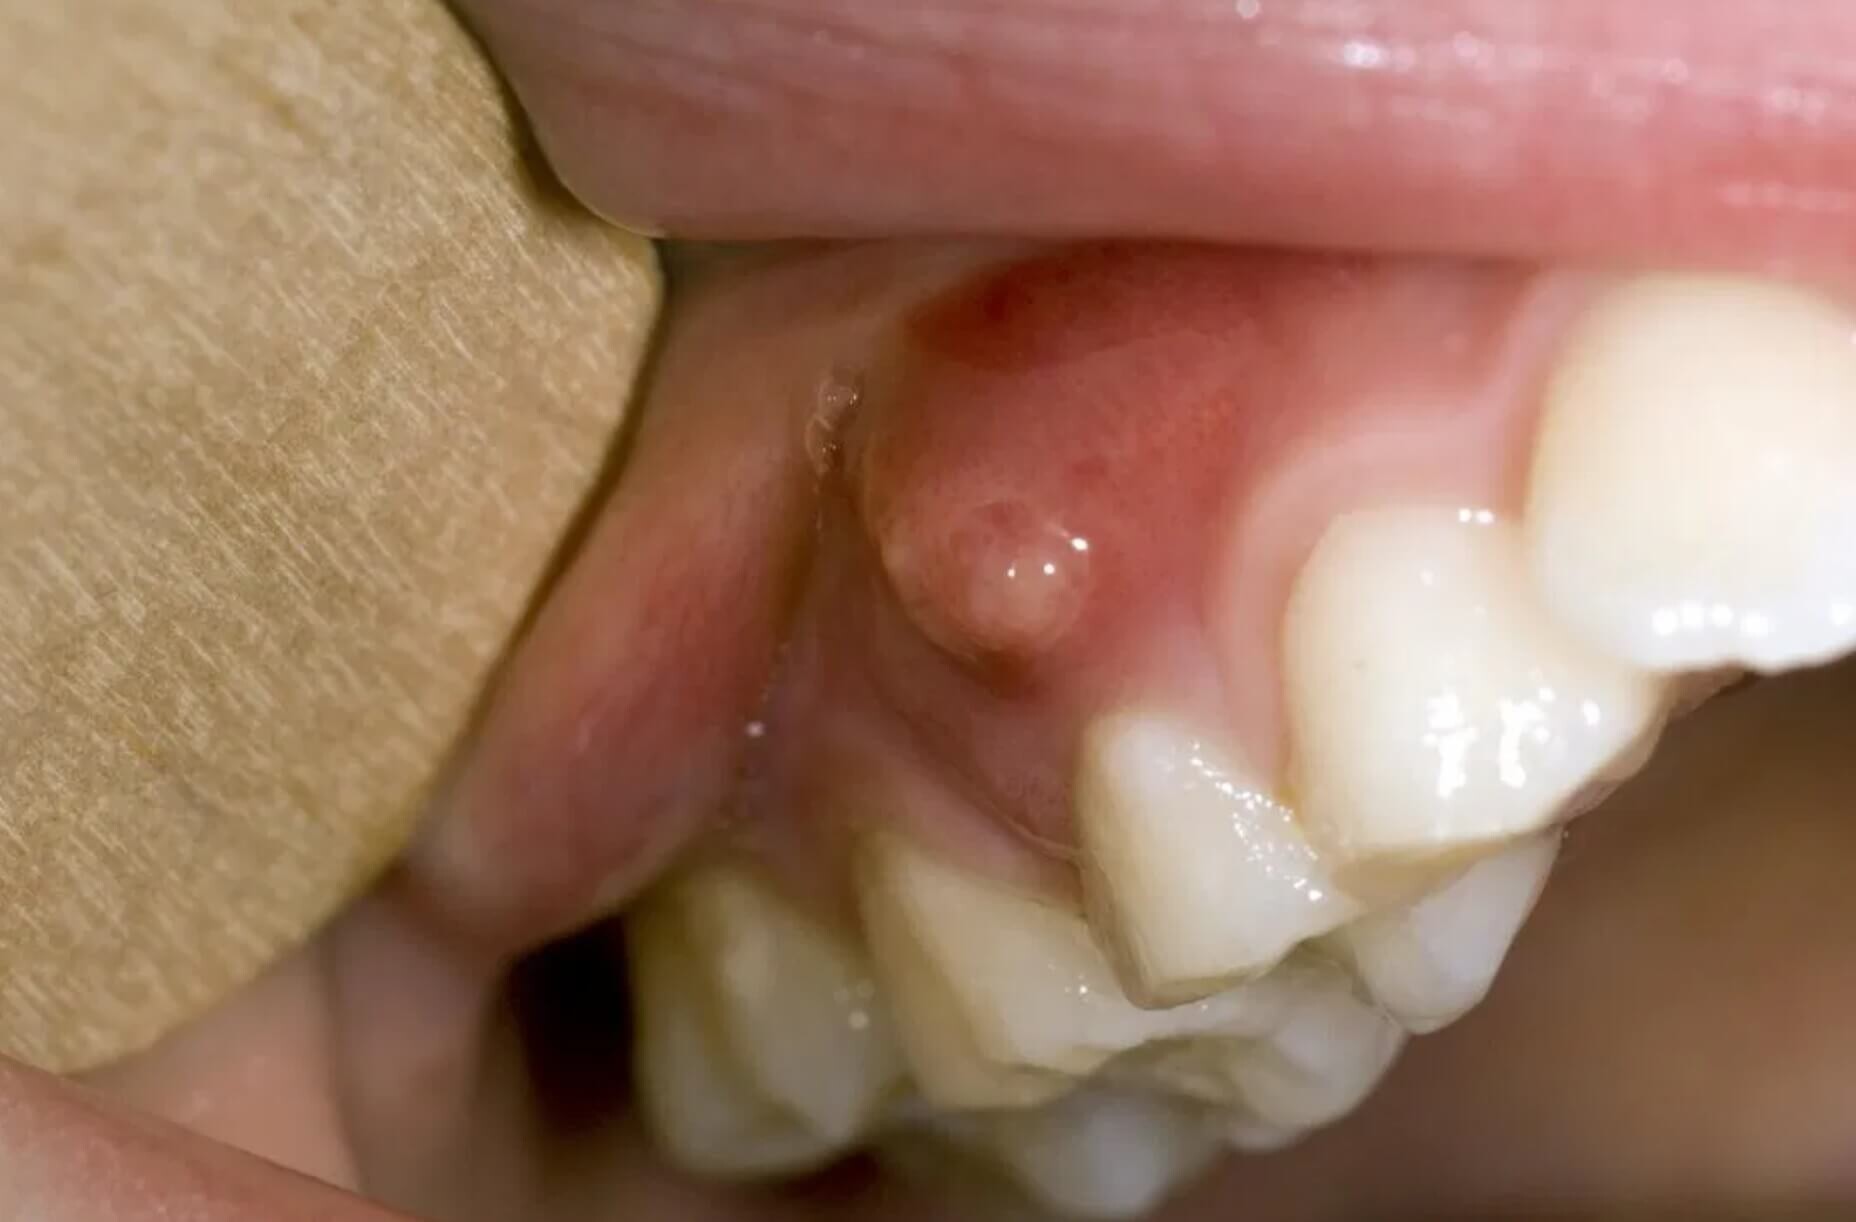

Gingival fistula: what is it and how is it treated?

Gingival fistula is an asymptomatic pathology, it is a lesion of the gingiva due to an oral cavity infection.

At its appearance the gingival fistula is a localized lesion of the gingiva, but if it is not treated with specific therapies it can extend to neighboring tissues and also affect the teeth, endangering the stability of the same.

Gingival fistula, if neglected, can lead to complications such as abscesses or dental fistulas. If in the first phase of its appearance does not present any symptoms, the aggravation of the pathology could result in acute pain in the area affected by the infection.